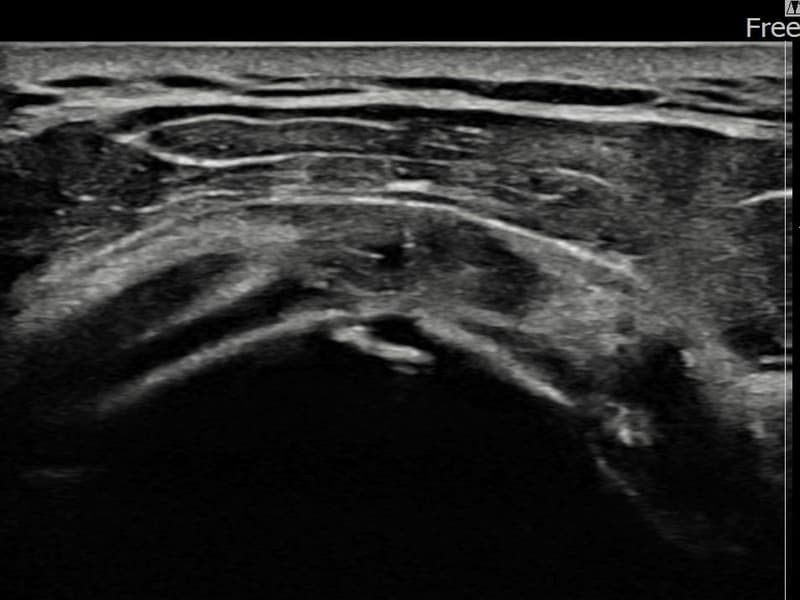

施術後

術前超音波にて左 棘上筋腱 関節面側部分断裂・左肩棘上筋腱のエコー不連続と腱欠損(8mm × 3mm (腱厚の約33%欠損))を確認。術後超音波では断裂部位が再生組織で充填され、腱の連続性回復とエコーパターンの正常化が確認されました。